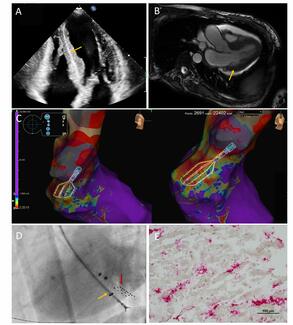

A 24-year-old female with history of an atrial septal defect post-patch closure (bovine pericardium) presented 4 years postoperative with an incidentally identified mass originating from the septal patch.

02/07/2024